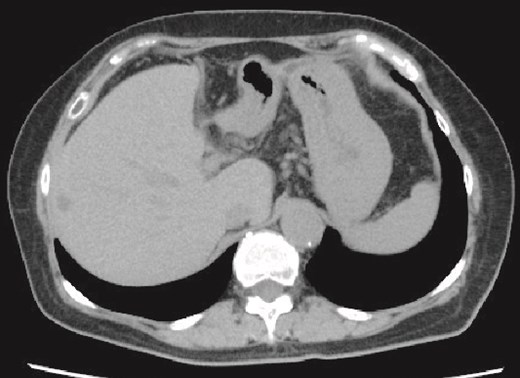

She was discharged home uneventfully on the 10th day after the surgery. CT has identified no evidence of recurrence 6 months postsurgery (Fig. 4).

Plain CT image 6 months after the patient’s surgery. There was no evidence of hepatic cyst recurrence.